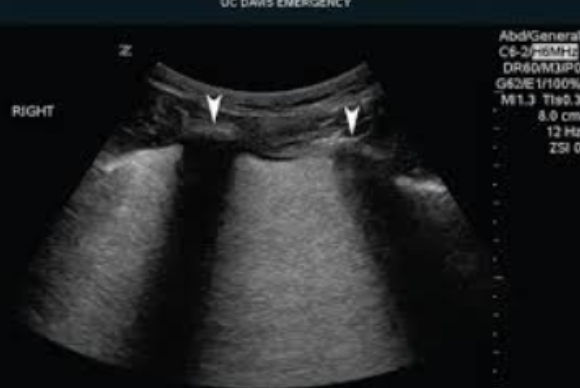

Reverberation

Occurs between two strong reflectors

Sound waves bounce back and forth between structures

Appears as equally spaced extra reflectors on the image

Commonly occurs in the anterior portion of the bladder

Reduced with harmonics (but can’t be completely eliminated)

strong reflectors, Sound waves, equally, bladder, harmonics, can’t

Occurs between two ___ ___

___ ___ bounce back and forth between structures

Appears as ___ spaced extra reflectors on the image

Commonly occurs in the anterior portion of the ___

Reduced with ___ (but ___ be completely eliminated)